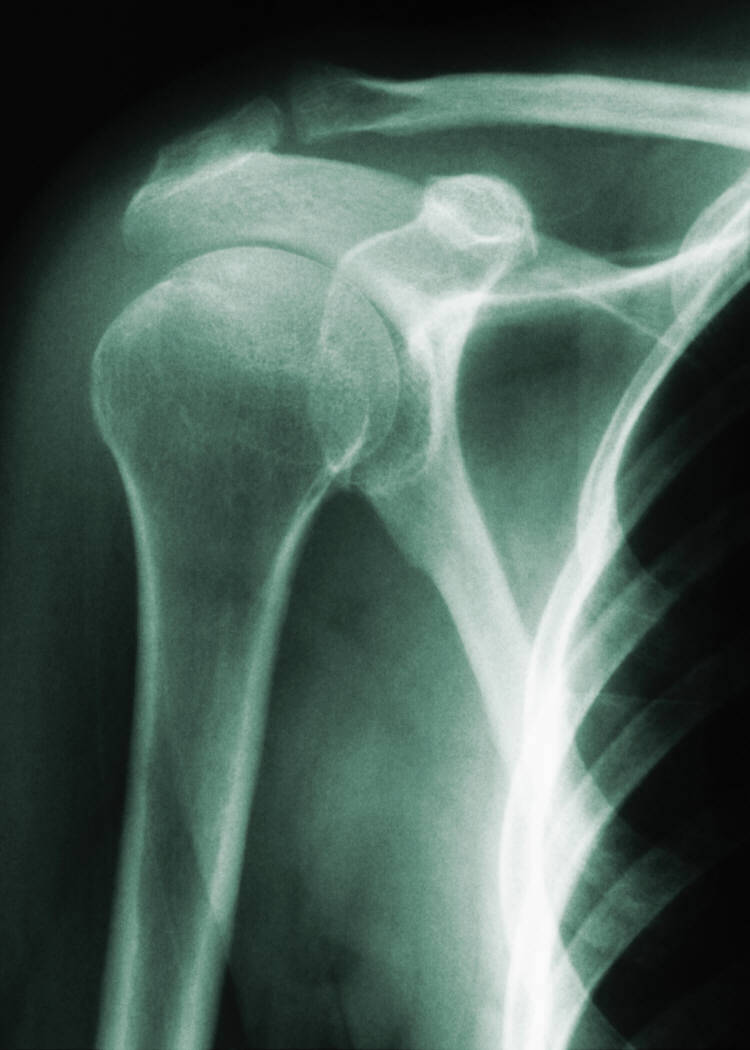

Рентген плеча: примеры снимков и их расшифровка